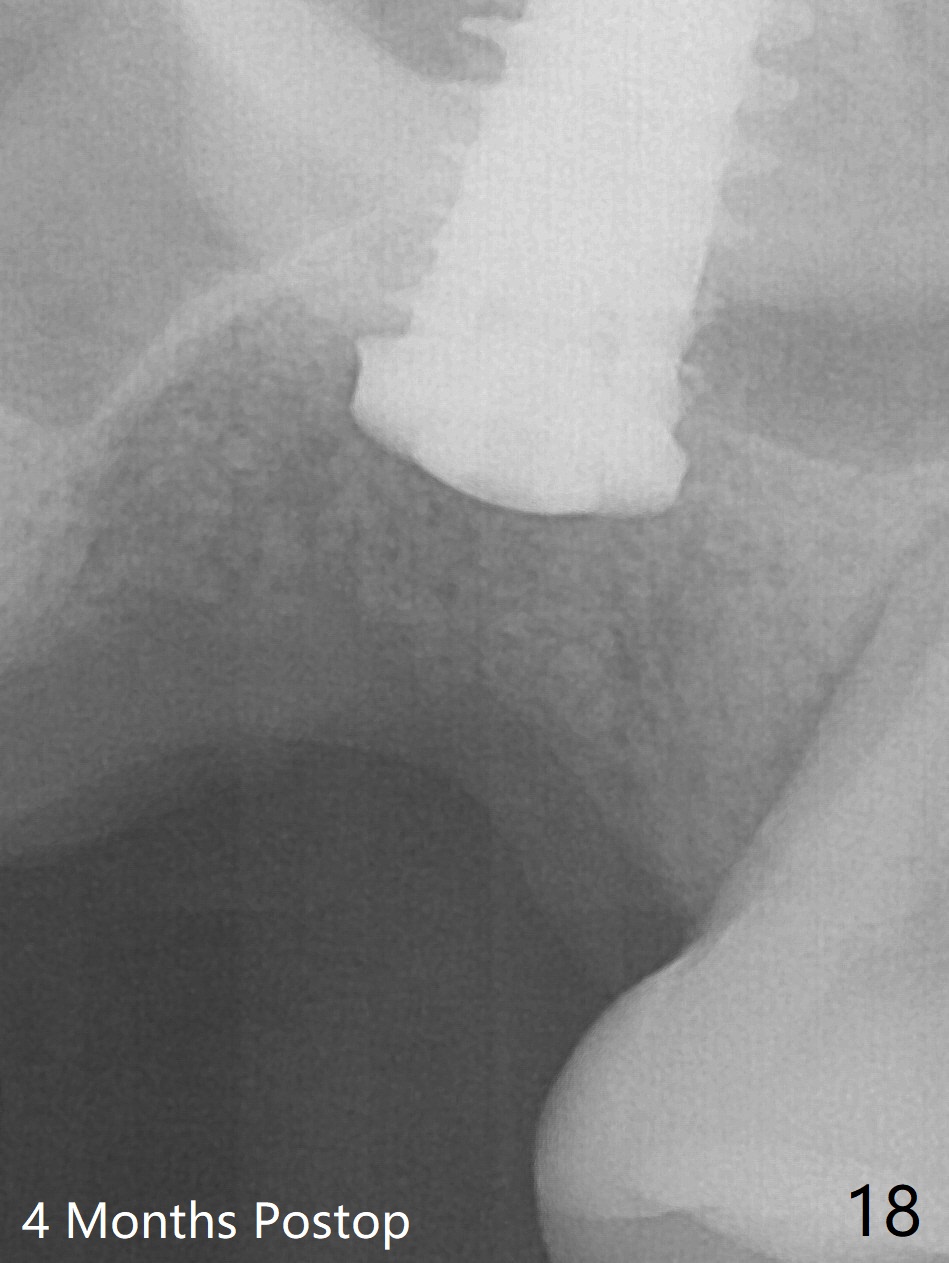

Poor visibility for immediate implant in the molar region is another contributing factor for the dislodgement.  The patient returns for follow up 15 days (Fig.15) and 1 month (Fig.16) postop.  Bone graft seems to be stable around the implant.  The socket heals 4 months postop (Fig.20).  The implant seems to have been osteointegrated (Fig.17,18).  It will be backed up for ~ 3 mm to improve implant/crown ratio (Fig.19, as compared to Fig.14).  If it cannot be done, take impression immediately and make a subgingival provisional before suturing.